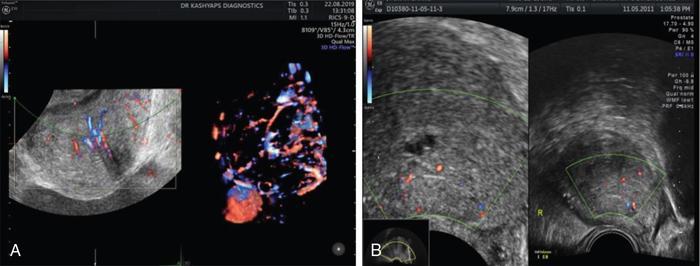

Benign prostatic hyperplasia

Prostatitis